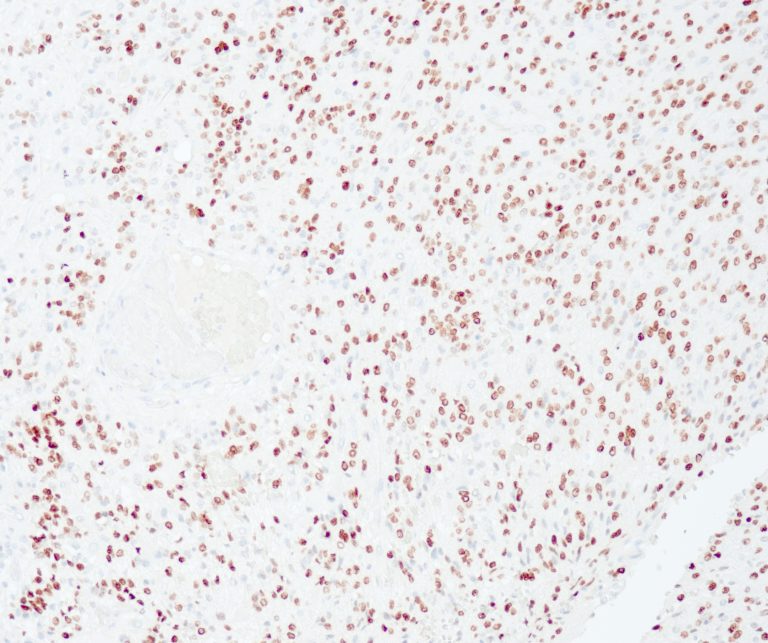

Hematopathology